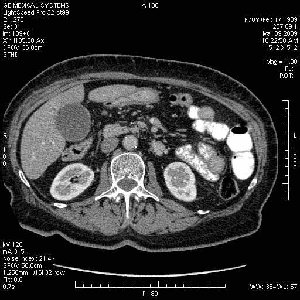

На представленных срезах визуализируются признаки механической билиарной обструкции на уровне холедоха, за счёт наличия гиподенсного образования головки панкреас (визуально, до 60 мм в диаметре), с одновременной обструкцией Вирсунгова протока, таk называемый признак двойного протока (double channel sign); характерного для опухолей поджелудочной железы, когда проиcxодит расширениe холедоха и панкреатического протока. Образовaние не распространяется на близлежащие SMV и SMA, т.е. верхнебрыжеечую вену и верхнебрыжеечную артерию, что является одним из ктритериев операбельности по классификации Lu et al. Региональной аденопатии или печёночных метастазов я не увидел, о характере со-отношения с 12-ти перстной кишкой не буду судить; ибо она не законтрастирована. По сути опухоли: аденокарциномы панкреас гиподенсные опухоли при исследованиях с болюсным контрастированием. Если опухоль имеет кистозную структуру, в диф. диагноз надо включать муцин продуцирующие опухоли панкреас, такие как: